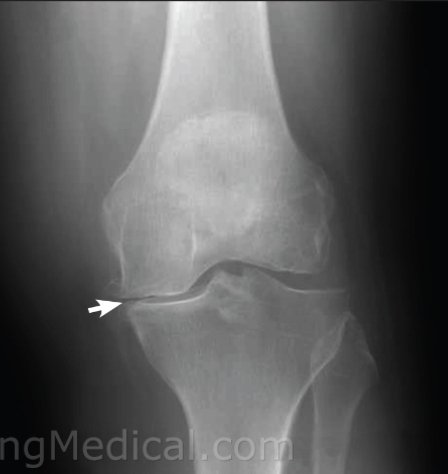

المرحلة المتقدمة : ألم مزمن ومستمر.

- عدم المقدرة على الحركة وصعوبة في المشي.

- ميلان في الركبة.